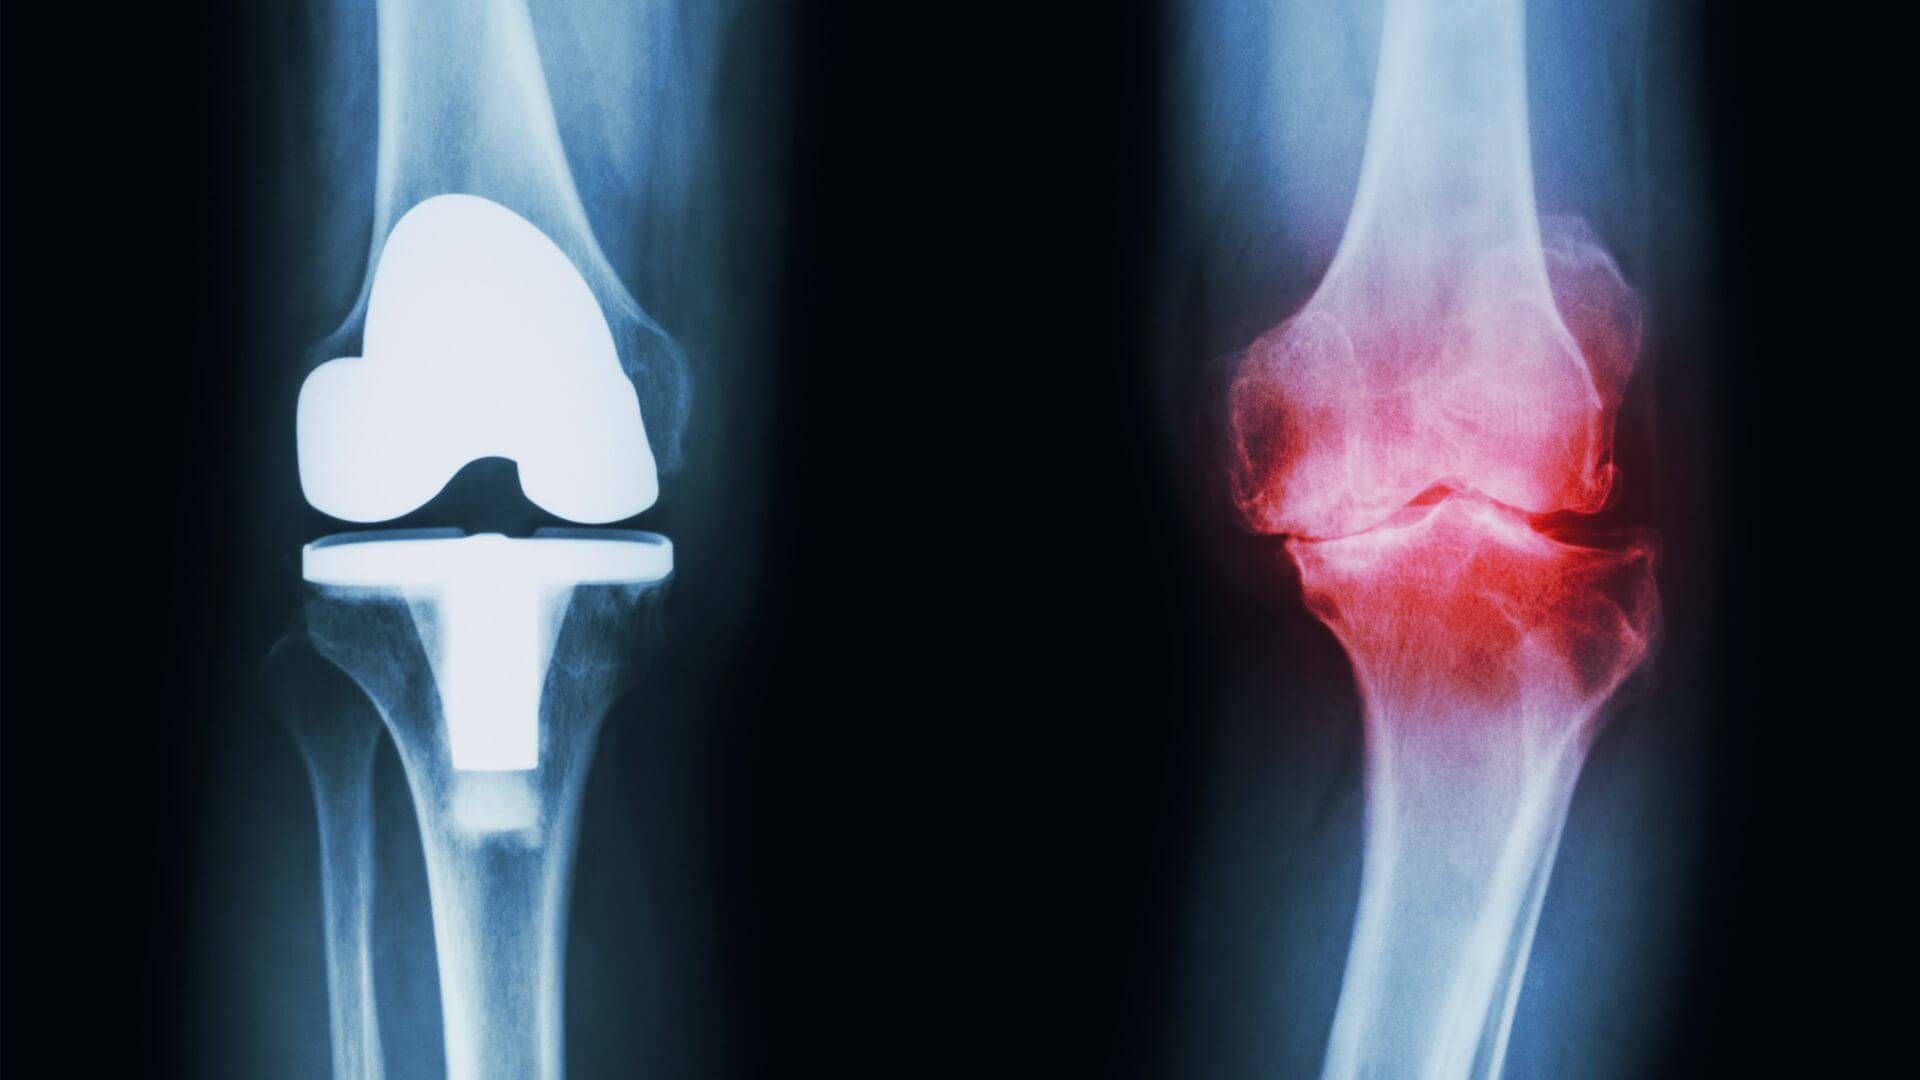

Em nossa região, nós fomos os pioneiros nas cirurgias de prótese total de quadril, joelho, videoartroscopia de joelho e intervenção na dor, com o objetivo de melhor atendermos nossos pacientes.

Tratamento de Osteoartrite de Joelho